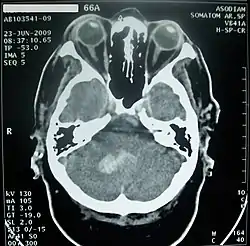

Кровоизлияние в мозжечок обычно проявляется головокружением, тошнотой и повторной рвотой при сохранении сознания. Больных часто беспокоит головная боль в затылочной области, у них обычно выявляются нистагм и атаксия в конечностях. При возникновении мозжечково-тенториального смещения или вклинении миндалин мозжечка в большое затылочное отверстие развивается нарушение сознания вплоть до комы, геми- или тетрапарез, поражения лицевого и отводящего нервов[44].